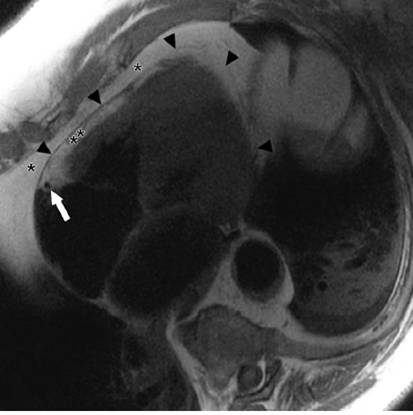

CT(非增强)Nongated unenhanced cardiac CT demonstrates

only minimal thickening of the pericardium up to 3 mm but presence

of linear pericardial calcification (white arrows) over the

right and left atrioventricular grooves suggestive of prior pericardial

process.

增厚的心包,胸水缩窄的症状

1个月激素治疗后,心包厚度正常